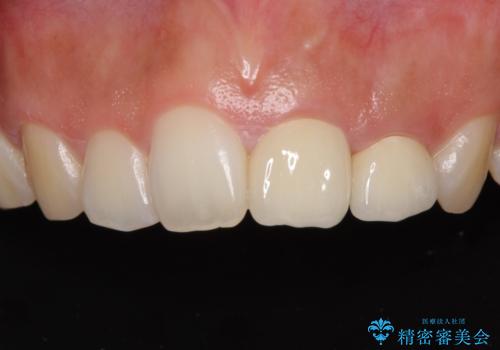

仮歯装着の時点で自然な見た目となり、オールセラミッククラウンを装着した際には、まるで自分の歯のようと喜んでくださいました。

長年変色を気にしており、もっと早くに治療を行えば良かったとおっしゃっていました。